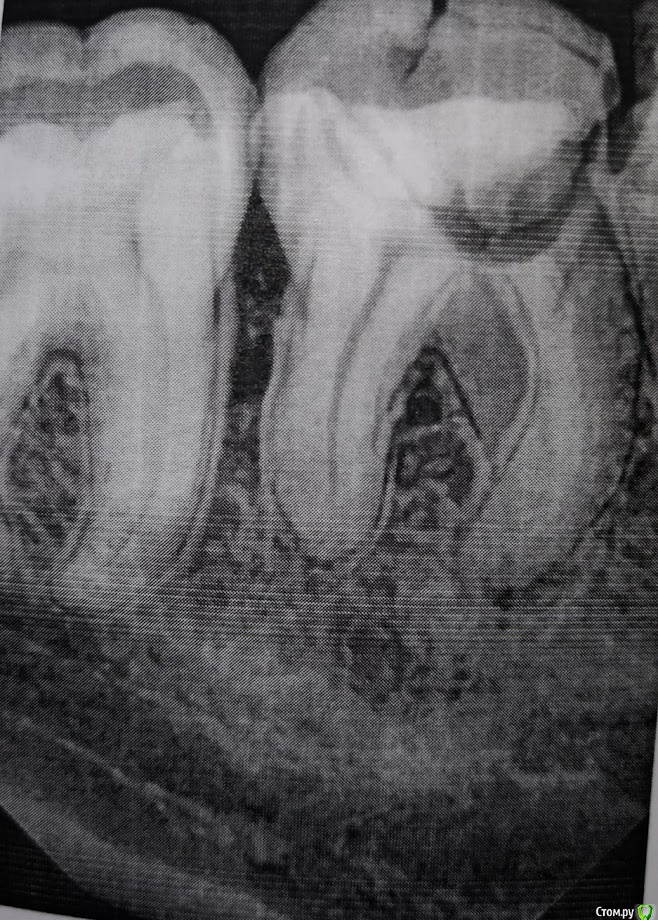

mdmm2 Опубликовано 27 февраля, 2019 Поделиться Опубликовано 27 февраля, 2019 Здравствуйте!Проблемы с правым нижним 6. Примерно 3 года назад зуб дал флюс. Тогда, в стоматологии, куда я обратился делали дренаж и порекомендовали удалить зуб, сказали, что каналы плохо пролечены и киста есть на всех 3 корнях. Флюс тогда прошёл, и я, как это часто бывает, забил на этот зуб, потому что больше он не беспокоил до сих пор. Примерно 2 недели назад, после переохлаждения, десна под зубом снова слегка припухла и начала болеть. Пил антибиотик доксициклин 9 дней (самолечение, глупо, знаю). Особо изменений ни к худшему, ни к лучшему нет.Сегодня решился удалить зуб и пошёл в гос. стоматологию. Там также сказали, что каналы пролечены плохо, но про кисту ни слова, и сказали, что зуб нужно пробовать лечить. Удалять не стали. Только умудрились открыть зачем-то каналы. Видно ли что-то из этой фотографии распечатки снимка, или она слишком плохого качества? Я хоть и не понимаю ничего в том, что изображено на снимке, но что-то мне подсказывает, что 3 года простоя этого зуба в ужасном состоянии, к тому же, открытие каналов сейчас, не оставляют значительных шансов на излечение. Ссылка на комментарий